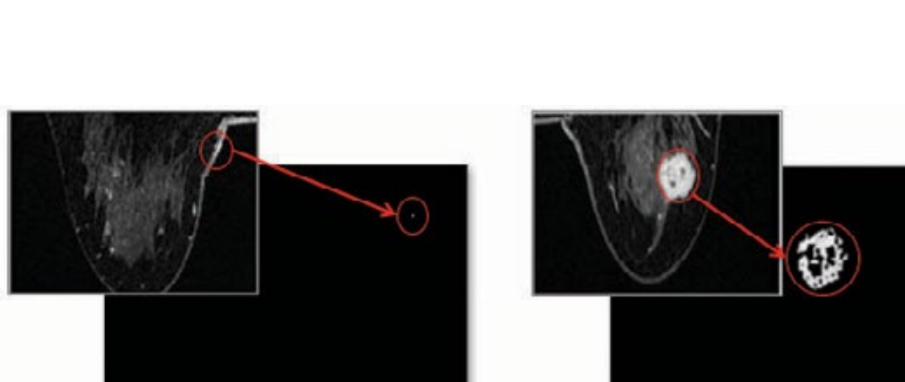

So after changing the images, how can we make it easier to see cancer from the image? Looking at figure 5 you can see exactly what I did. After figuring out the max difference area from the previous step, I changed the rest of the color to black and left the most different area to white. As you can see the picture without cancer(Left) has little to no white space at all while the picture with cancer (On the right) shows a massive amount of space with white color.